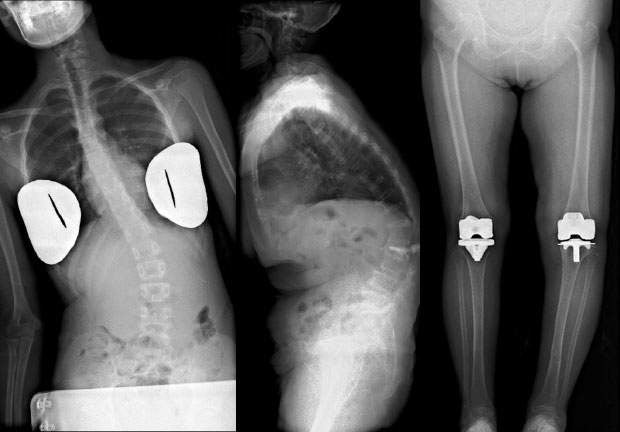

Long-length imaging is an essential radiography technique in the field of orthopedic surgery for the diagnosis of scoliosis and alignment measurements on the full length of the lower limbs. At this hospital, we conduct radiography with multiple IPs loaded in a long-length cassette and join the images together when reading them.

Conventional CR long-length imaging is difficult for patients who have trouble standing, as it is difficult to achieve adequate SID from the table and to maintain the long imaging field. It is also difficult in cases where a wide imaging field is required, such as patients with severe scoliosis and radiography of both legs simultaneously. With its 1,400mm FPD movement range and 430mm wide coverage, Slot Scan flexibly accommodates a diverse range of radiography examinations (Fig. 4). As many scoliosis patients are young, it is important to reduce the X-ray exposure dose over follow-up examinations over many years.